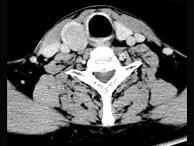

问题 男,43岁,因右颈部扪及一包块来院就诊。如图所示该患者应诊断为 ( )

选项 A、甲状腺原发淋巴瘤 B、甲状腺转移瘤 C、甲状腺腺癌 D、结节性甲状腺肿 E、甲状腺腺瘤

答案 E